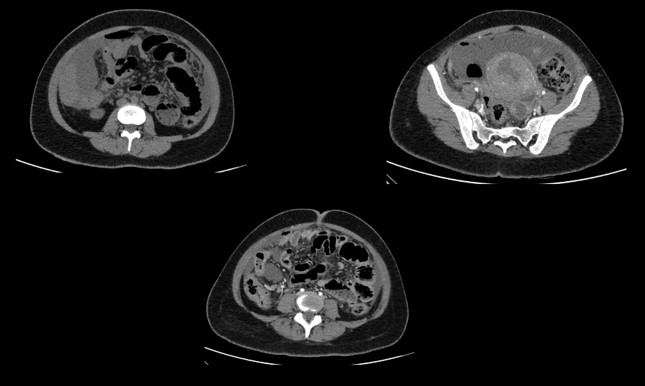

• Axial and sagittal CECT images of the abdomen in delayed phase.

• On delayed imaging, the contrast is seen extravasating (red arrow) from the upper pole calyx (suggesting calyceal rupture) into the perirenal space and retroperitoneum (green arrow).

• Omental caking and peritoneal thickening seen in left lower quadrant. (red arrow)Short segment narrowing of the left distal ureter with abrupt cut off. (green arrow)